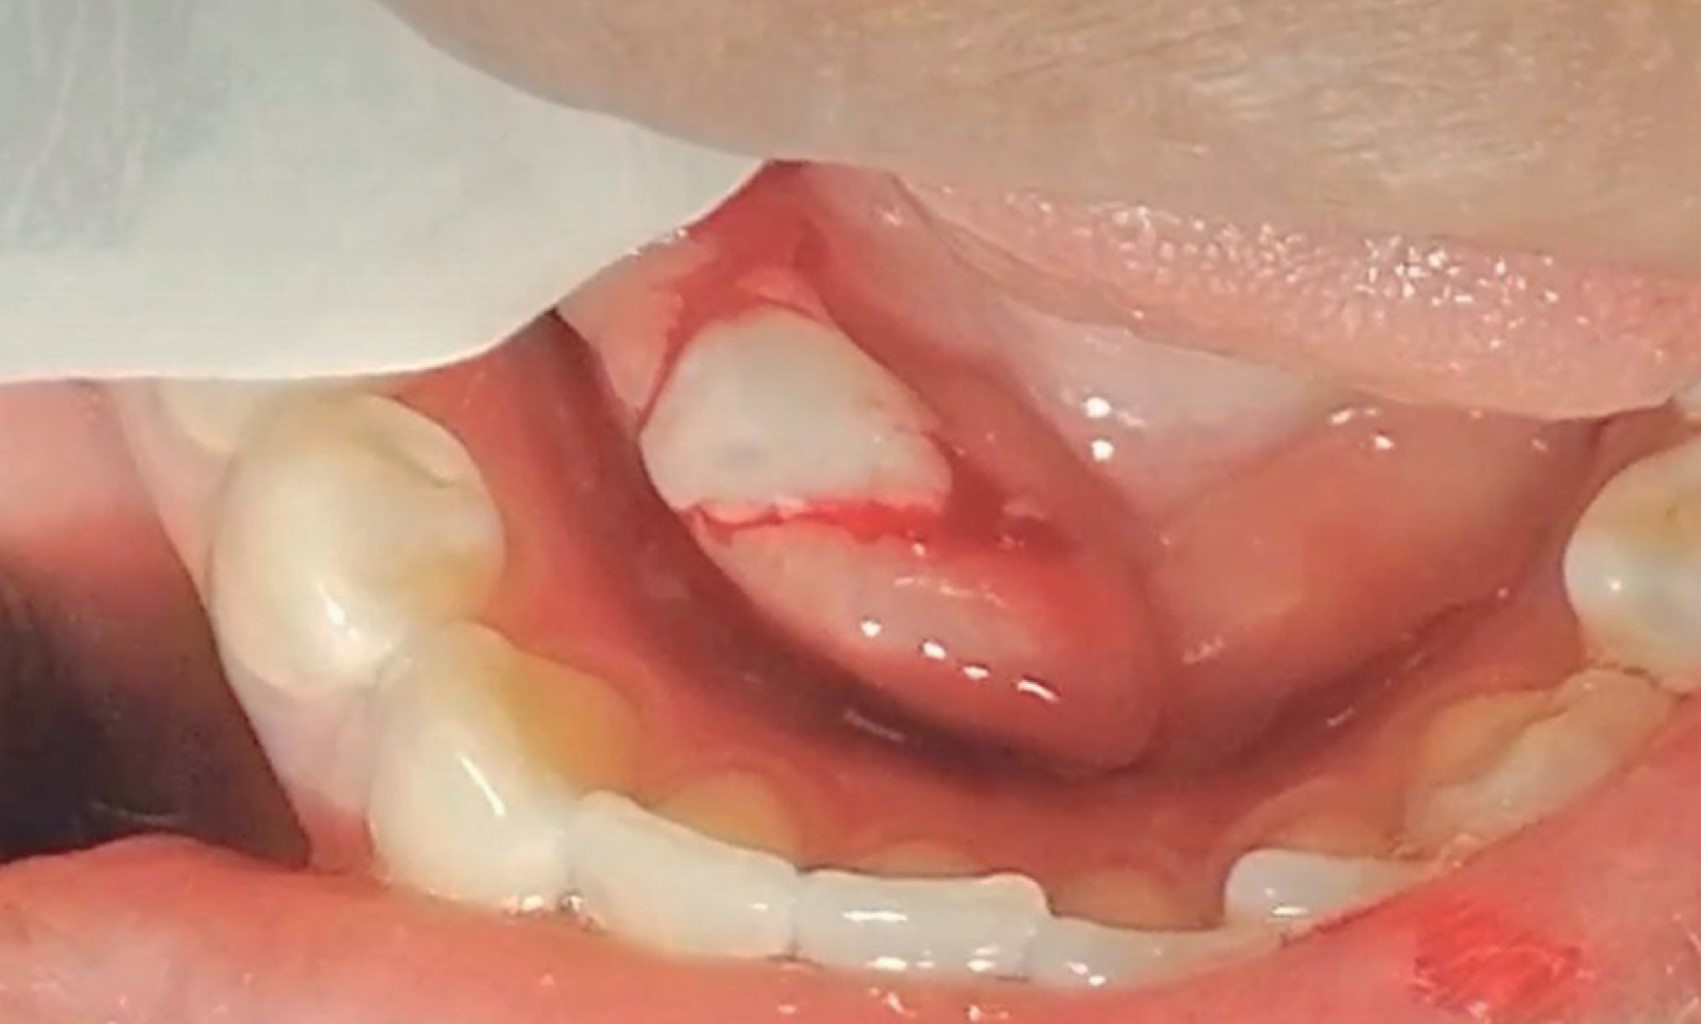

Previa infiltración de lidocaína 2% 1:100,000 haciendo bloqueo nervioso del nervio lingual, después se realizó una incisión lineal de 1 cm en la porción más prominente del sialolito sobre la mucosa, medial y paralela al trayecto del conducto de Wharton y del nervio lingual (Figura 4). Mediante unas pinzas mosquito (Halsted) se llevó a cabo la disección roma en dirección al sialolito la cual generó la expulsión del mismo en su totalidad fuera del conducto submandibular (Figura 5). Se realizó maniobra de digitopresión para ordeñar la glándula, con la finalidad de drenar la saliva estancada en el conducto submandibular, al momento de realizarla se observó salida de material purulento (Figura 6). Se efectuó la limpieza del lecho quirúrgico mediante irrigación con solución electrolizada de superoxidación. Se suturó la herida con Vicryl 4-0 mediante dos puntos simples (Figura 7). Por último se volvió a hacer la maniobra de digitopresión para observar la adecuada permeabilidad de la carúncula. La sialolitotomía se llevó a cabo sin complicaciones. En el postoperatorio inmediato se recetó antibiótico y analgésicos antiinflamatorios. La paciente fue citada siete días después de la intervención quirúrgica para su revisión postoperatoria. A la exploración no había presencia de inflamación extraoral, así como ausencia de infección, dolor, sangrado y dehiscencia de la herida quirúrgica (Figura 8).

Figura 6